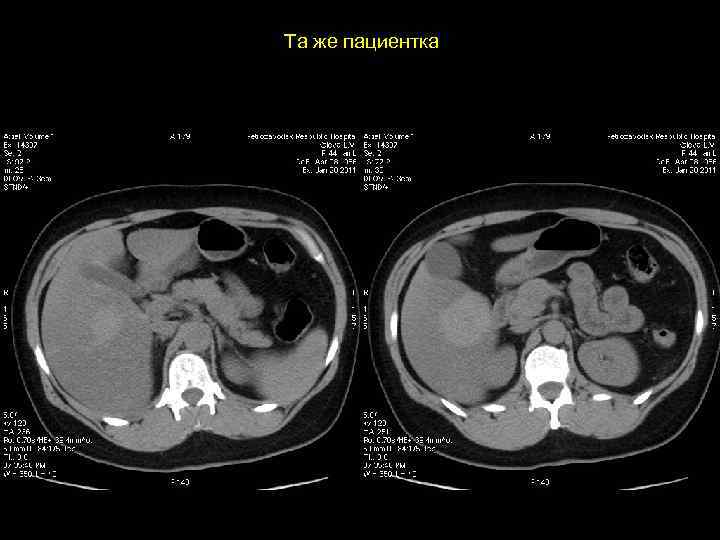

Та же пациентка

АКТУАЛЬНЫЕ ВОПРОСЫ РЕНТГЕНОЛОГИИ ЛУЧЕВАЯ ДИАГНОСТИКА ОЧАГОВЫХ ПОРАЖЕНИЙ ПЕЧЕНИ ФОКУСНАЯ (УЗЛОВАЯ) ГИПЕРПЛАЗИЯ ПЕЧЕНИ Магнитно-резонансная семиотика: - образование с гипоинтенсивным сигналом на Т 1 взвешенных изображениях с ободком - образование с гиперинтенсивным сигналом на Т 2 взвешенных изображениях